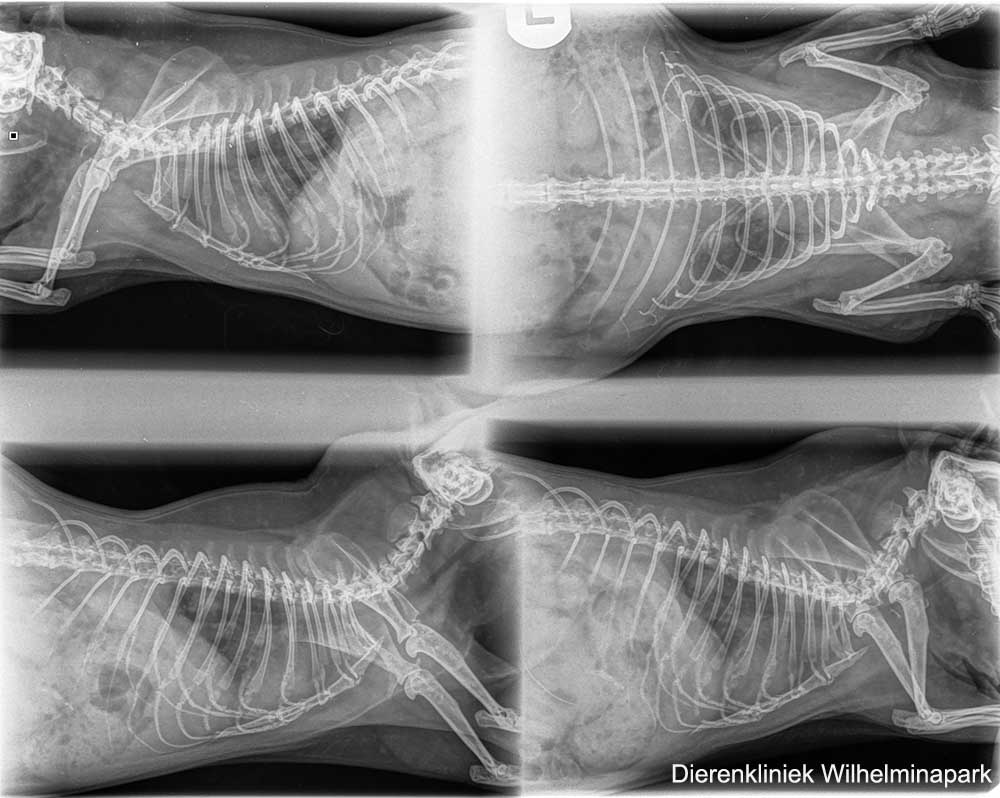

Cavia Tygo was benauwd - er was een zware ademhaling te zien en er was een bijgeluid te horen bij de ademhaling.

Tygo kreeg doxycycline als antibioticum.

De beoordeling van de röntgenfoto: er is een sterke aanwijzing voor een longprobleem. Dan kiezen we voor een ander antibioticum als behandeling.

Tweety had al drie soorten antibioticum gekregen, maar deze sloegen onvoldoende aan.

Bij cavia Tweetie is er er op de röntgenfoto's een aanwijzing van een hartprobleem te zien.

We hebben de röntgenfoto's laten beoordelen: er is een verdenking van een pericard overvuulling. Het hart is vergroot op de röntgenfoto, het advies is om een echo te maken. Met een echografisch onderzoek is een pericardovervulling goed te zien. Er zit dan vocht tussen het hart en het hartzakje.